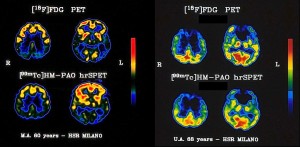

Una memoria che zoppica non è la prima spia del morbo di Alzheimer. Uno studio dell’Università del Kansas (Usa) ha scoperto che un improvviso declino di altre capacità del pensiero o dell’apprendimento può costituire un segnale d’allarme anni prima della diagnosi. In particolare, sembra che a ‘saltare’ per prime siano abilità come quelle necessarie per leggere una mappa o completare un puzzle. Lo studio, pubblicato sugli ‘Archives of Neurology’, può aiutare i medici a identificare segni di Alzheimer a uno stadio precocissimo, cruciale affinché i farmaci oggi disponibili abbiano un impatto significativo.

Così i risultati hanno mostrato che le abilità visuospaziali – necessarie per percepire la distanza tra gli oggetti – inizia a declinare rapidamente tre anni prima della diagnosi. Mentre un calo generale nelle capacità mentali è stato osservato l’anno successivo. Invece il declino della memoria non si è manifestato nei pazienti fino a un anno prima della diagnosi clinica.